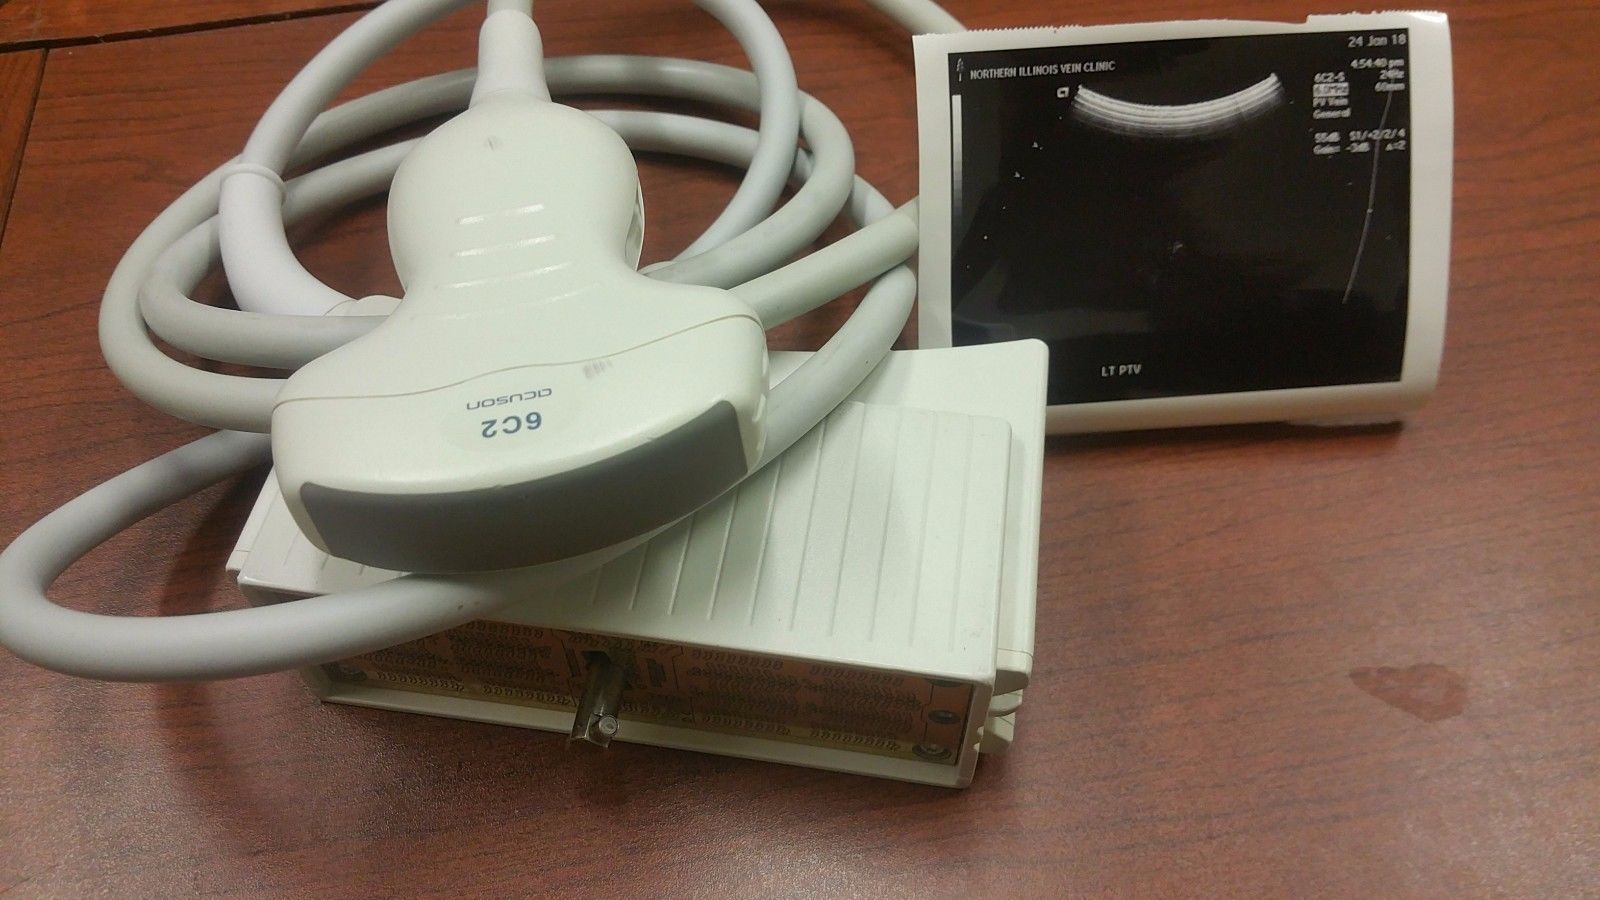

Acuson 6C2 Ultrasound Probe Transducer

The Acuson 4C1 Ultrasound Transducer Probe is a high-performance convex array probe designed for a wide range of clinical applications, including abdominal, obstetric, and gynecological imaging. Engineered for superior image clarity and deep tissue penetration, this transducer ensures accurate diagnostics with high-resolution imaging. Compatible with select Acuson ultrasound systems, the 4C1 probe offers excellent reliability and durability for continuous medical use. Its ergonomic design provides ease of handling, making it an essential tool for healthcare professionals seeking precision and efficiency in patient diagnostics. Whether replacing an existing transducer or upgrading your ultrasound equipment, this probe guarantees seamless integration and optimal performance. Each unit is tested and verified for quality assurance, ensuring consistent results in demanding medical environments. Available for fast shipping and competitive pricing, the Acuson 4C1 Ultrasound Transducer Probe is a trusted choice for professionals looking for accuracy and reliability in diagnostic imaging. Contact us today for pricing and availability.

Condition: Used